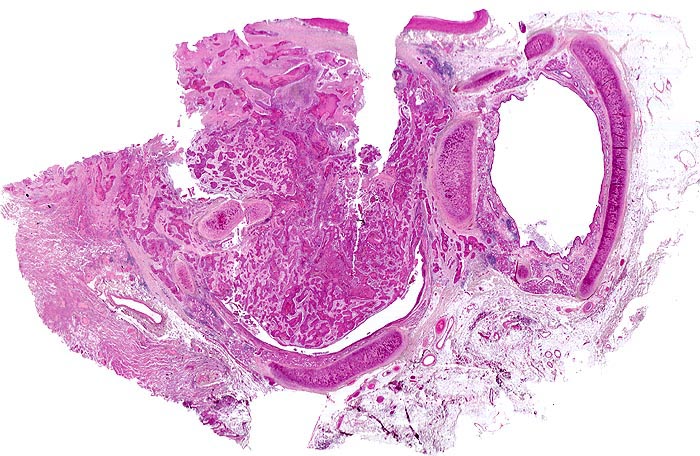

PathoPic – image database / PathoPic ID 4724 - Plattenepithelkarzinom

Plattenepithelkarzinom

Lunge

Eine Bronchuslichtung von einem Tumorzapfen weitgehend verschlossen. Rechts davon ein tumorfreier Bronchusquerschnitt. Das Tumorgewebe bildet solide Zellstränge, welche eingebettet sind in ein desmoplastisches Stroma. Zusammengequetschtes Lungengewebe am Rand der Probe.

Zentrales Bronchuskarzinom des rechten Lungenoberlappens von 5cm Durchmesser. Lungenoberlappenresektion.

Das Präparat zeigt den tumorbefallenen Bronchusresektionsrand. Die Resektion erfolgte also nicht im Gesunden.